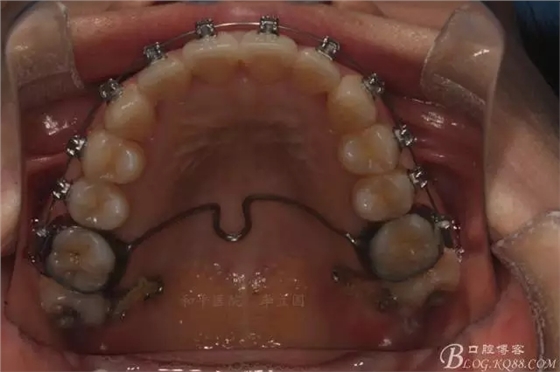

如圖,該病例為簡(jiǎn)單排齊病例,但77鎖合是矯治中的關(guān)鍵所在,你會(huì)怎么處理?

該病例主要為17、27頰側(cè)位同時(shí)伴有伸長(zhǎng),當(dāng)然種植支抗可以解決,但還有簡(jiǎn)單實(shí)用的辦法嗎?如圖,在橫腭桿遠(yuǎn)中延伸出牽引鉤,位置盡量遠(yuǎn)離合平面,7粘舌側(cè)扣,牽引力的方向?yàn)閴旱图吧嘞?,下圖為兩個(gè)月的效果,17已到位,27還未到位。